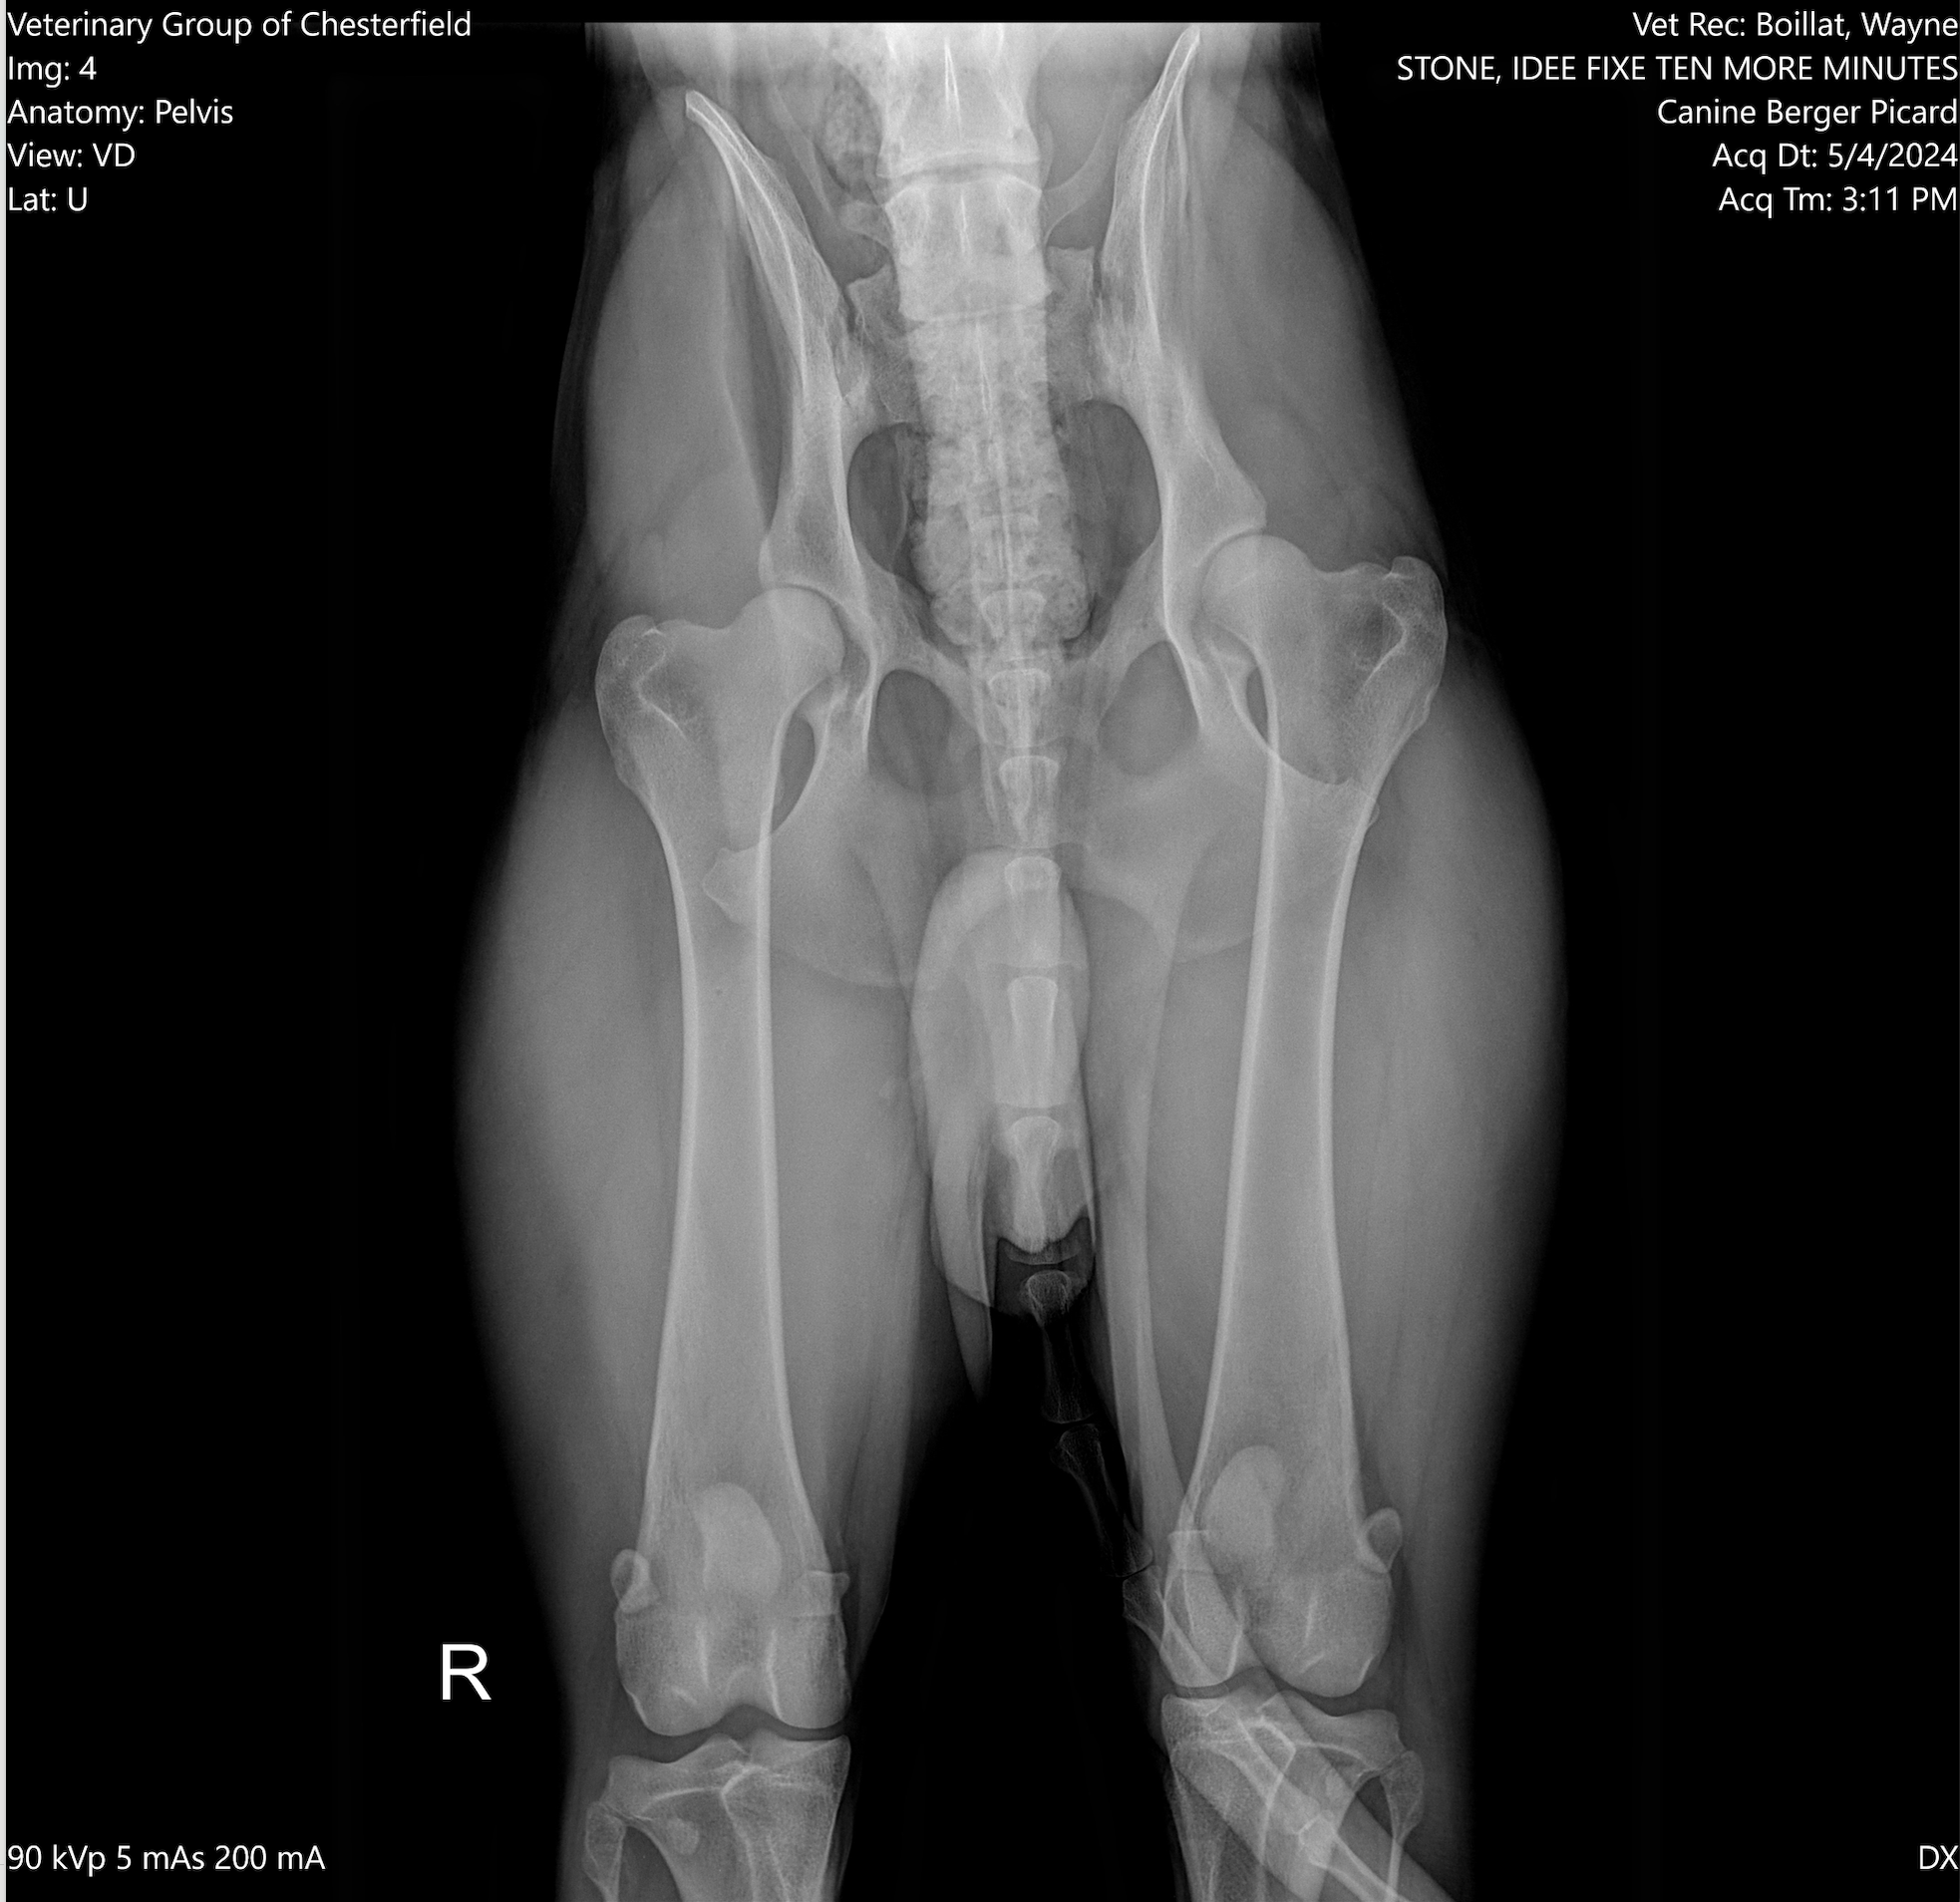

OFA Hips ---

PennHip ---

Excellent

---- OFA Hip & Elbow Imaging ----